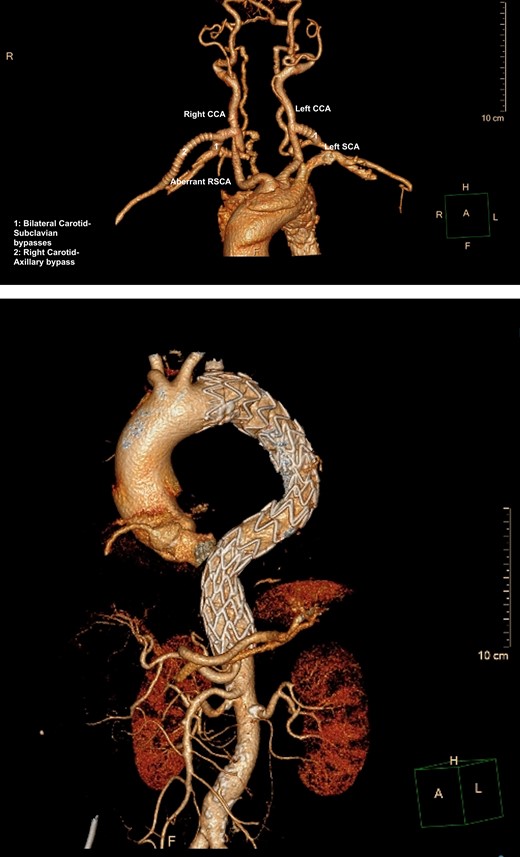

Despite optimal anti-impulse therapy, the patient had refractory chest/upper back pain. The patient underwent a left C-S bypass and right subclavian to common carotid artery transposition (with oversewing of proximal subclavian stump). This was followed by deployment of covered thoracic endovascular graft (Navion, Medtronic) from left common carotid artery (CCA) to 5 cm proximal to celiac artery proximally. The left subclavian artery was occluded using endovascular plugs. His postoperative 2-week CT showed good stent apposition and no endoleak (Fig. 4A, B). He was discharged Day 14 and returned to regular work at 1-month time interval.

(A) 3D-CT reconstruction showing post op repair and Right subclavian to carotid transposition. (B) 3D-CT reconstruction showing post op repair and left C-S bypass.